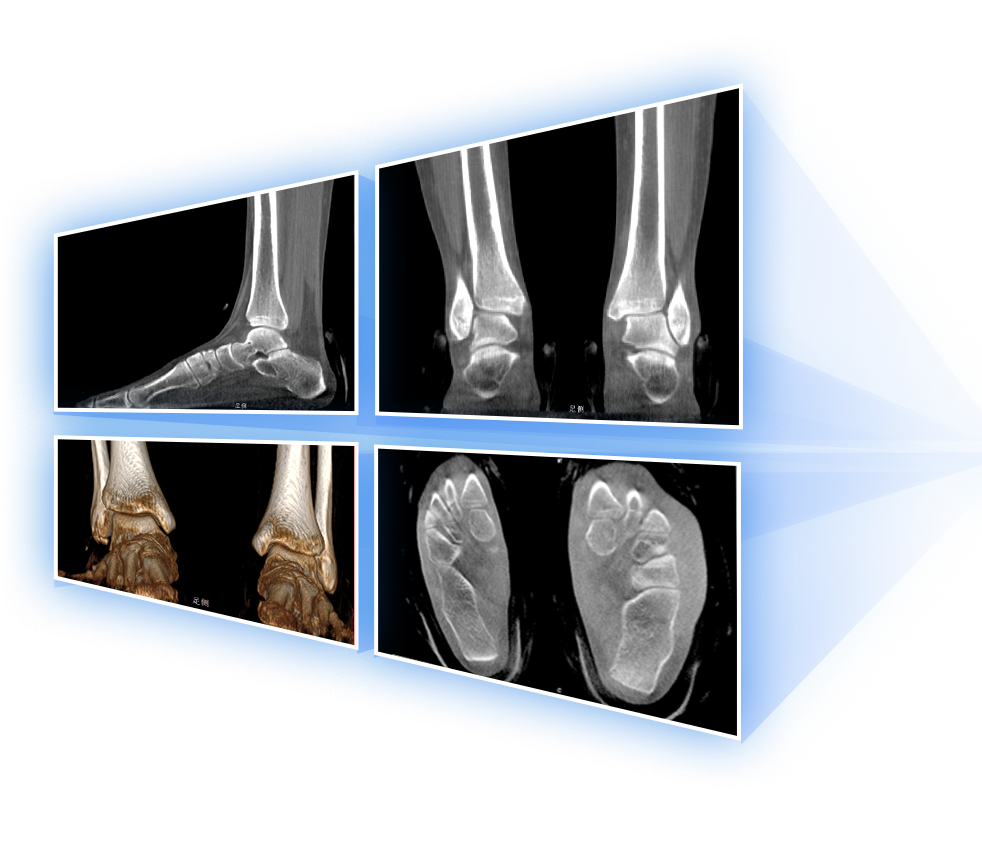

· 补位CT,提供负重位三维影像

· 引领普放走向三维精准诊断时代

填补常规CT/MR空白

助力术前规划和术后评估

足踝

精准诊断

手术方案规划

术后随访

VR体绘制重建